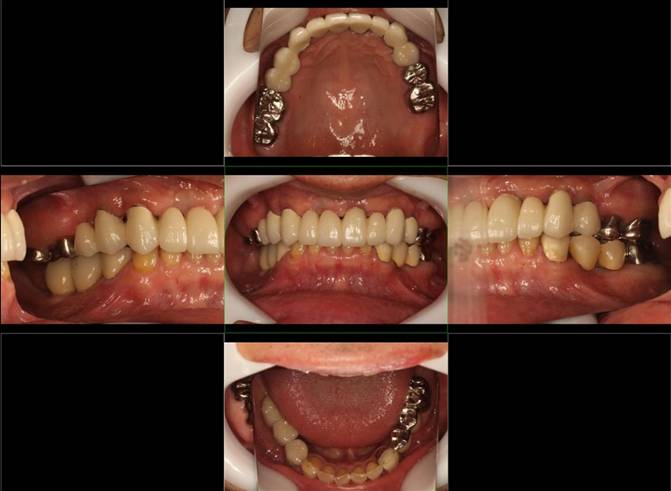

歯周病で抜歯せざるを得ず、インプラントを希望されたケース(使用インプラントはスプライン)

術前。すべての歯が歯周病の末期状態でブリッジ全体がうごいて噛めないとの訴え。右上の犬歯が腫れていました

固定式のブリッジが入っていましたが歯周病で動いています

下顎前歯部には歯石の沈着がみられます

術後。上部構造はハイブリッドレジンです。しっかり嚙めるようになり喜んでいただきました。

上部構造装着後6年。ハイブリッドレジンを使用したため、少し艶がなくなってきました。上部構造の材料には金属、ハイブリッドレジン、セラミックなどがあります。セラミックはきれいですが欠けやすいため、最近はフルジルコニアを使っています。

上顎 少しすり減ってきました。

下顎。12か月に一度メインテナンスをしています。

インプラント装着後6年。順調に経過しています。12か月毎のメインテナンスをしています。